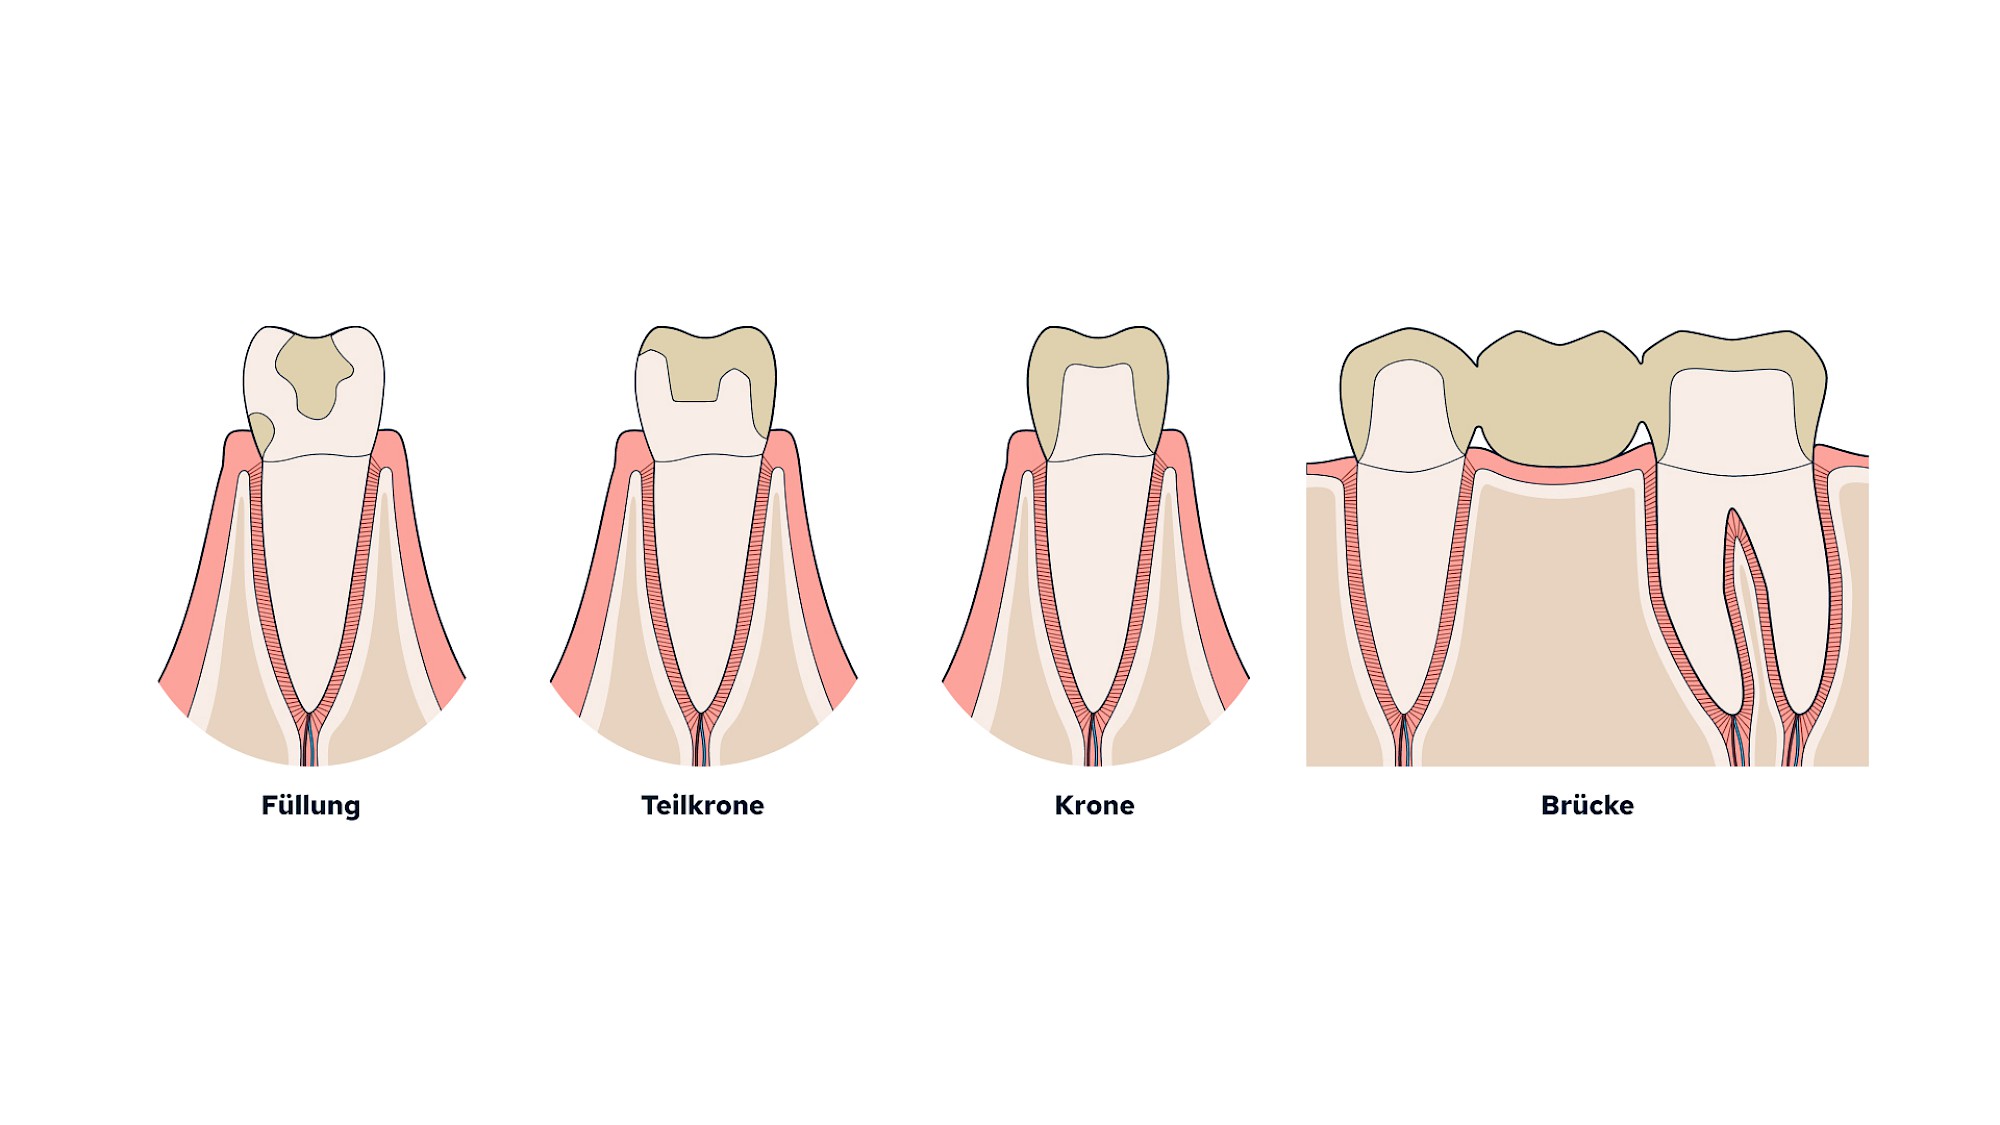

Wenn Zähne "Löcher" haben oder gar fehlen, kann der Zahnarzt die Zähne entweder mit Füllungen bzw. (Teil-)Kronen versorgen oder die fehlenden Zähne mit Brücken wieder ersetzen. Immer häufiger werden fehlende Zähne durch künstliche Zahnwurzeln (Implantate) mit künstlichen Zahnkronen darauf versorgt. Alle diese Versorgungen werden fest im Mund verankert und können z. B. zur Nacht oder zur täglichen Mundpflege nicht herausgenommen werden.

Zahnfüllung, Krone & Brücke